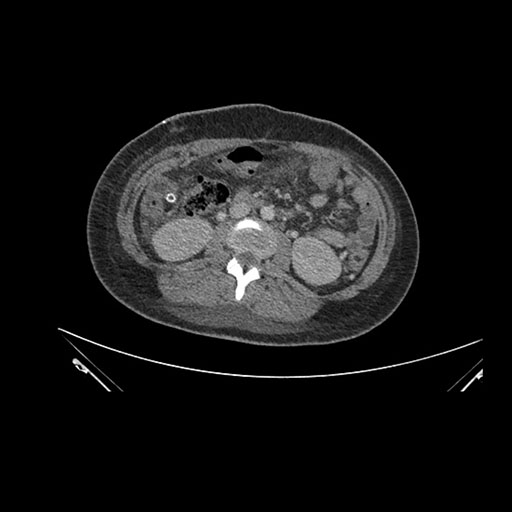

Look through the patient's CT scan to identify any areas of concern for the necessary procedure.

Imaging analysis

Based on initial findings, which issue(s) would you be most concerned about?